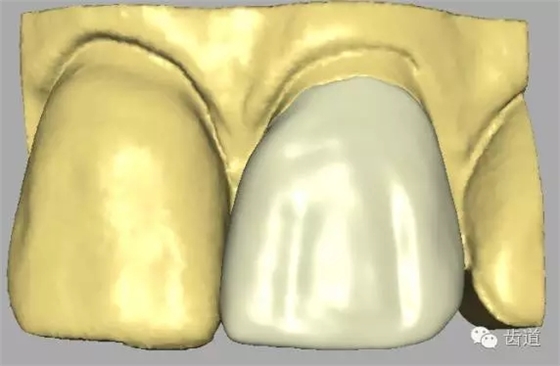

二)確認(rèn)在代型上完全就位:

全冠僅邊緣與代型接觸,其余內(nèi)表面與代型表面間隙大小為30-40μm。

四)人造冠就位 1、理論標(biāo)志

人造冠內(nèi)表面與患牙面間隙不大于50μm。 2、參考標(biāo)志

1)人造冠齦邊緣達(dá)設(shè)計(jì)位置。

2)咬合基本合適

3)就位后穩(wěn)定無翹動